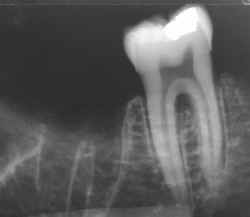

Identificação Humana por Comparação Computadorizada de Imagens

Radiográficas Dentárias